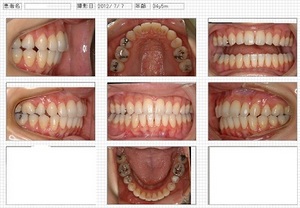

顔貌、口腔内写真の評価 上下のズレが大きい

終了時写真

治療期間:2年01ヶ月

治療総費用:852000円(税込)

上下顎前突症治療例

13歳女性 主訴は横顔

治療前: 歯ぐきの傾斜が上下ともに強いことがよく分かります。

治療後:

①歯と歯ぐきは整直 ②口唇閉鎖不全(口が閉じにくい状態)改善 ③横顔改善

治療期間:2年10ヶ月

治療総費用:730500円(税込)

上顎前突治療例(30代 女性)

主訴 ①出っ歯、②横顔を鏡で見たとき口元が出ている

分析 歯の前方傾斜が標準値より大きい、口唇が標準値より突出している

治療方針 歯の傾斜と横顔、そしてズレを改善するために抜歯治療を選択

治療前

治療後

横顔

治療前

治療後

治療期間:2年01ヶ月

治療総費用:852000円(税込)